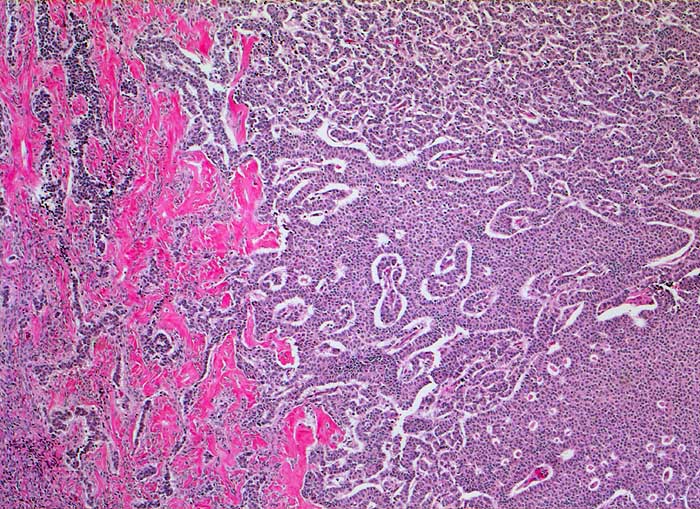

Granulosazelltumor vom adulten Typ

maligner Tumor

Ovar

Teils trabekuläres, teils solides Wachstum mit zahlreichen Call Exner Körperchen.

Die Tumorzellen zeigen eine Positivität für Inhibin und CD99, sind jedoch negativ für EMA.

Ovarial-Tumor links -> Adnexektomie links. Frage: Dignität? CA-125 im Normbereich.